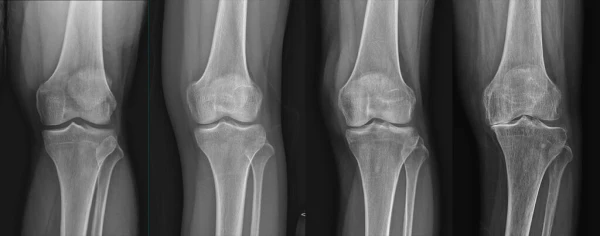

통풍이란 요산이 체내에 쌓여 관절에 염증을 일으키는 질병으로, 관절이 혹처럼 튀어나와 보일 정도로 심한 증상을 유발한다. 통풍이라 불리는 이 질병은 고통스럽고 찌르는 통증을 동반하며, 바람이 불면 더욱 심해지는 것이 특징이다. 이러한 고통은 주로 밤이나 새벽에 나타나며, 급성인 경우 일주일에서 한 달 동안 지속될 수 있다. 만성적인 경우에는 요산배설촉진제를 사용하여 치료된다.

통풍을 적절히 치료하지 않을 경우, 발작성 관절염의 빈도가 증가하고 침범하는 관절 수도 더 많아지며, 회복에 필요한 시간도 증가합니다. 반복적인 관절염은 관절을 점차 손상시키며, 만성적인 관절염으로 진행될 수 있습니다. 또한 통풍성 결절이라 불리는 덩어리가 관절 주위나 피부 조직에 나타날 수 있습니다. 이러한 결절은 요산 결정체의 덩어리로 어느 부분에서든 형성될 수 있으며, 주로 팔꿈치, 귀, 손가락, 발가락, 발목 등에서 발생할 수 있습니다. 때로는 요로 결석을 형성하기도 합니다.

1) 한 군데 관절(엄지발가락, 발목, 무릎 등)이 갑자기 붓고 빨갛게 변하며, 손을 움켜쥘 수 없을 정도로 심한 통증이 발생합니다.

4) 엄지발가락 관절에 염증이 잘 발생하는 것이 특징이며, 무릎, 발, 발목, 손목, 팔꿈치 등 다른 관절에서도 발생할 수 있습니다.